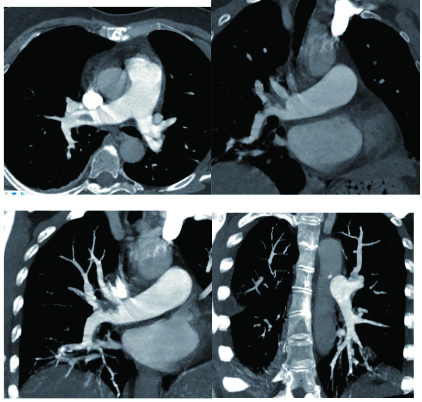

1 经典的挽救性溶栓治疗策略可能带给医生更多的是被动和难度例1 男性,28岁,体质量90 kg。主诉“胸闷、憋气1周加重1 d”。既往:体健;喜久坐(平均10~15 h/d);否认手术史、外伤史;入院查体:神志清楚,体温36.8℃,血压128/80 mmHg(1 mmHg=0.133 kPa),脉搏120次/min,呼吸26次/min,脉氧饱和度96%(安静,空气氧),未见明显乏氧征。双肺呼吸音清,未闻及干湿性啰音。心率120次/min,心律齐,P2 > A2,心界无扩大,无杂音。腹软,无压痛,肠鸣音正常,双下肢无浮肿。神经系统查体未见异常。血气分析(空气氧)提示pH 7.514,PaCO2 27.2 mmHg,PaO2 67.1 mmHg,SaO2 95.0%;D-Dimer:3 035 ng/mL,FDP 33.08 μg/mL,FBG 4.520 g/L;PLT 179.0 G/L,TNI 0.08 ng/mL,BNP 882.00 pg/mL;ALT 38 U/L,AST 17 U/L,CREA 82.6 μmol/L,血Na+、K+、Cl-正常范围;超声心动图(Ultrasonic Cardiogram,UCG)提示:右心增大,肺动脉主干及右肺动脉增宽,肺动脉主干32 mm,三尖瓣反流(重度),反流面积8.6 cm2,TI法估计SPAP为67 mmHg、左室舒末内径50 mm、左室E/A:45/38 cm/s, 左室壁厚度及运动正常,未见节段性室壁运动障碍;双下肢静脉超声提示左侧股静脉血栓形成可能(完全型)。心电图(图 1所示)提示窦性心动过速;肺动脉增强CT(Computed tomographic pulmonary angiography, CTPA)提示双肺主干明确充盈缺损(图 2所示)。入院诊断:急性肺血栓栓塞症(中高危)。入院后给予抗凝治疗(依诺肝素钠90 mg,皮下注射,1次/12 h)重叠华法令治疗的第4天D-Dimer升至47 482 ng/mL,第6天2 411 ng/mL。第7天常规复查双下肢超声未见新增血栓形成,复查UCG(当天INR 2.25)提示右心房漂浮血栓,并随心脏蠕动明显(图 3所示)。在准备胸外科手术取栓的过程中出现血压下降至70/40 mmHg,脉氧饱和度降至45%,立即给予气管插管并系统溶栓治疗(r-tPA 100 mg于2 h输注),溶栓治疗1.5 h患者血压逐渐回升并趋于稳定、溶栓治疗3 h自主呼吸开始恢复,于插管3天后(住院第10天)拔出气管插管,成功撤离呼吸机。溶栓过程中曾经出现消化道、气道出血,血红蛋白下降1.9 g/dL,未予输血治疗。溶栓后复查CTPA提示双肺主干血栓负荷明显减少,远段血液灌注明显增加(图 4所示)。

| 图 2 入院时CTPA提示双肺主干明确充盈缺损 |

| 图 4 溶栓后的CTPA肺动脉主干血栓负荷明显减少、远段血液灌注明显增加 |

患者特点及感悟:①该例患者是非常经典的中高危PE患者,抗凝治疗期间出现血流动力学不稳定并接受挽救性溶栓治疗的成功案例。患者入院时明确诊断为急性PE(中高危),生命体征稳定,按照指南指导下的抗凝治疗没有任何原则性问题。很有意思的问题是:住院后第1次D-Dimer 2 511 ng/mL,抗凝治疗的第4天D-Dimer升至47 482 ng/mL(>正常高限200倍),第6天降至2 411 ng/mL,住院期间患者并无任何不适,血压稳定,心率波动100~120次/min左右。入院第7天常规复查UCG提示右心房漂浮血栓。理论上讲,D-Dimer水平与血栓负荷成正比(纤溶系统正常),入院CTPA显示的血栓负荷量能否解释入院初D-Dimer?入院后第4天D-Dimer超过正常高限200倍时提示自身纤溶系统激活还是充分抗凝治疗期间依旧没有控制高凝状态导致持续新的血栓形成?当D-Dimer降至10倍高限时发现了新的血栓脱落至右心房。这样的结果提示急性期PE患者D-Dimer的巨大波动,高度提示有新发血栓形成的可能,应给予相应的检查,避免进一步血栓脱落出现致死事件发生。②右心房血栓的病死率报道36%,但是右心房血栓目前意见并不一致[7-9]。本例为抗凝达标(INR 2.25)时的发现右心漂浮血栓,原则上手术开胸取栓更为合理并可以避免栓子堵塞三尖瓣或肺动脉主干后导致猝死的发生。但因为准备手术期间,瞬间出现呼吸窘迫、氧合下降、血压骤降等危险时,被迫溶栓只能是一搏。很显然,这样的结果尚不能随意外推出后面的结论:一旦出现右心漂浮血栓都可以从系统溶栓治疗中获益。但至少说明治疗期间的密切的D-Dimer水平监测、定期的UCG检查和必要时的双下肢静脉超声检查有助于帮助医生进行准确的判断。③患者出现生命体征急剧恶化时,心率始终处于100~120次/min,对于青年患者而言虽然没有不适主诉,在排除其他原因的情况下,很可能成为预示病情存在潜在危险的信号。